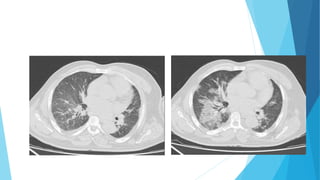

Características da Imagem